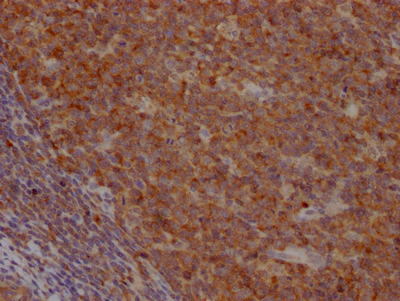

• IHC image of CSB-RA833808A0HU diluted at 1:100 and staining in paraffin-embedded human tonsil tissue performed on a Leica BondTM system. After dewaxing and hydration, antigen retrieval was mediated by high pressure in a citrate buffer (pH 6.0). Section was blocked with 10% normal goat serum 30min at RT. Then primary antibody (1% BSA) was incubated at 4℃ overnight. The primary is detected by a Goat anti-rabbit IgG polymer labeled by HRP and visualized using 0.05% DAB.